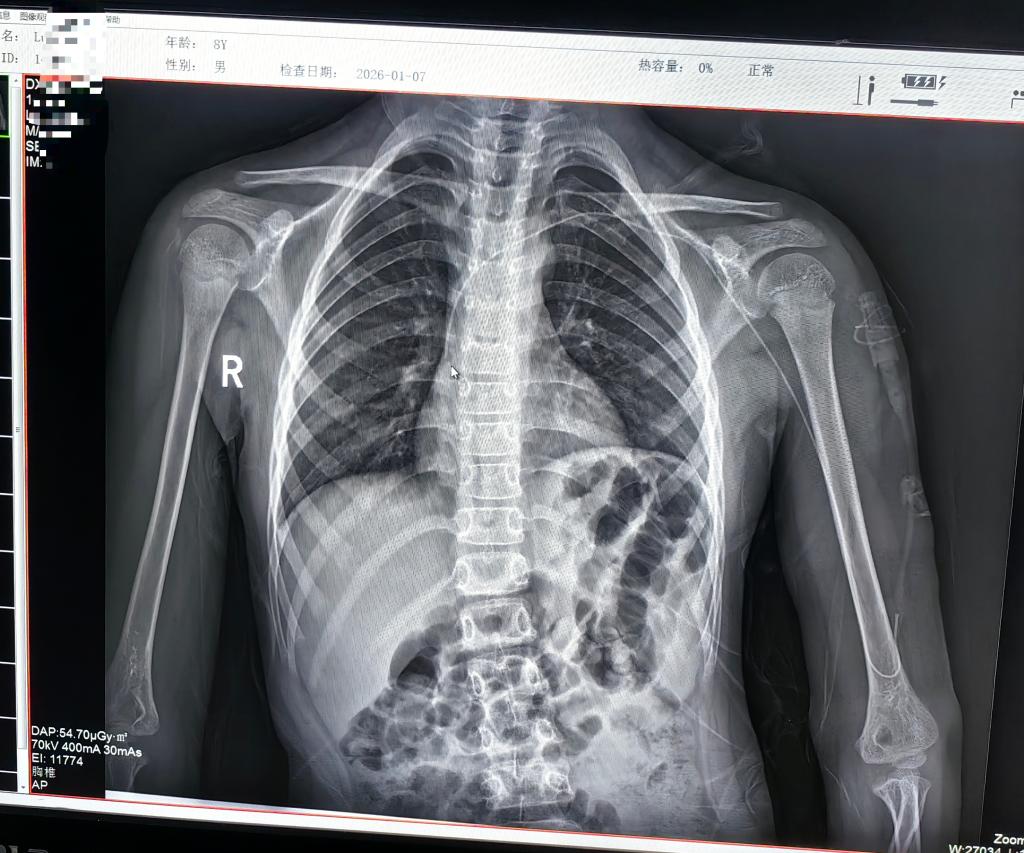

儿童PICC置管难度远超成人,患儿血管细、配合度低、皮肤娇嫩,对操作精准度和医护沟通能力均提出极高要求。术前,医护团队通过游戏互动缓解患儿的紧张情绪;在超声医学科栗玉娇主治医师的精准定位下,静疗专科组长赵强强(普外科)护士长,带领团队选择左侧头静脉作为穿刺点,助手吴楠主管护师温柔固定患儿肢体,操作者凭借熟练的技术,穿刺一针见血、成功送管,术后经胸片确认,导管尖端精准位于上腔静脉中下1/3段,置管后当天即可顺利输液,患儿状况良好。“再也不用看着孩子每次穿刺哭着挣扎了,太感谢你们了!”朵朵父亲握着医护人员的手激动地说。